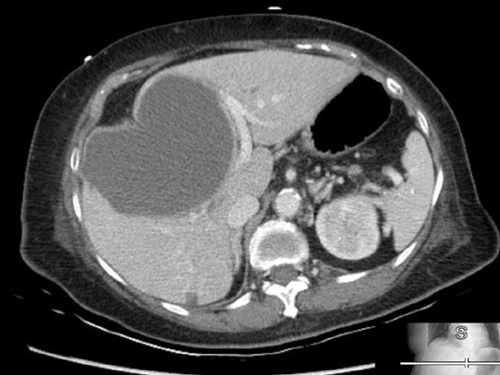

Imaging: Portable CXR showed mild cephalization of the vessels and blunting of costophrenic angles bilaterally.

Point-of-care sonography was performed in order to assess volume status and the following representative image was obtained